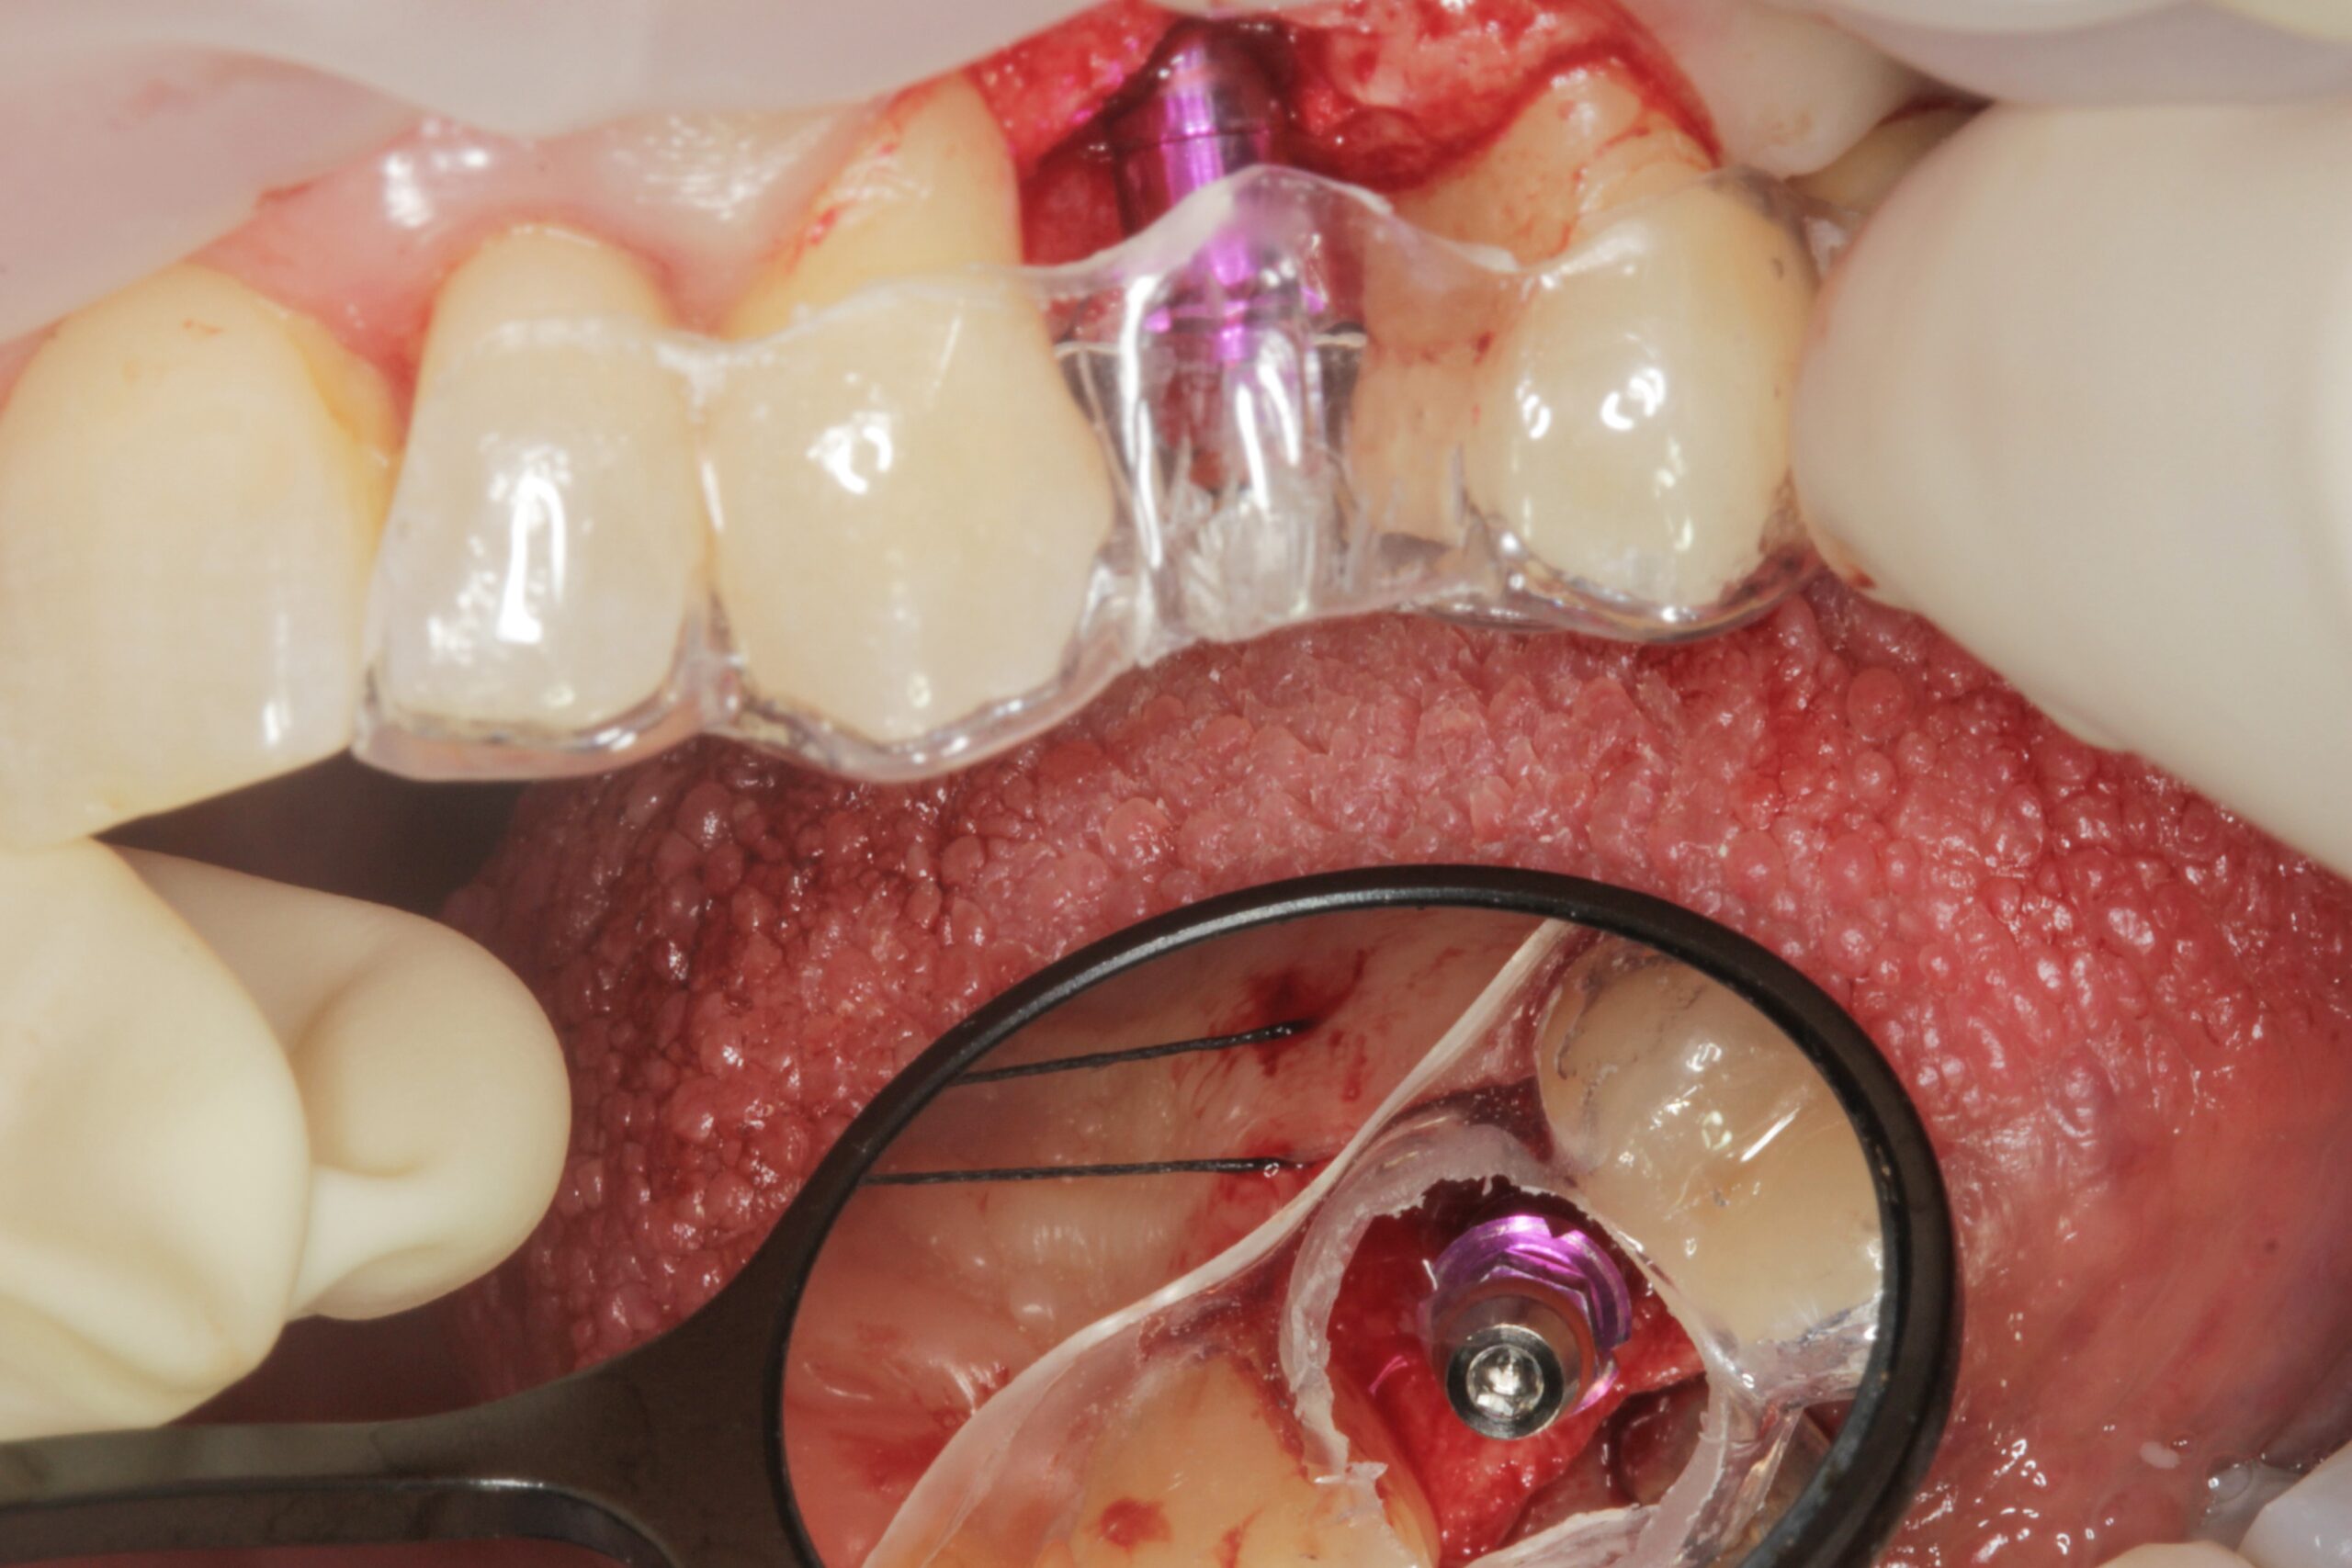

Métodos: Se llevó a cabo un caso clínico en una paciente de 40 años con fracaso de restauración fija dentosoportada en el incisivo central superior izquierdo, asociado a caries radicular subgingival con mal pronóstico restaurador. Tras la evaluación clínica y radiográfica, se indicó la exodoncia atraumática del diente afectado. Inmediatamente después, se realizó la colocación de un implante postextracción. El defecto periimplantario (gap) fue rellenado con un xenoinjerto óseo bovino. De forma simultánea, se llevó a cabo un injerto de tejido conectivo con el objetivo de optimizar el volumen y la estabilidad de los tejidos blandos periimplantarios. Se procedió a la colocación de una restauración provisional inmediata atornillada, diseñada para preservar el perfil de emergencia y guiar la cicatrización de los tejidos periimplantarios. Tras un periodo de cicatrización de cuatro meses, se colocó la restauración definitiva atornillada.